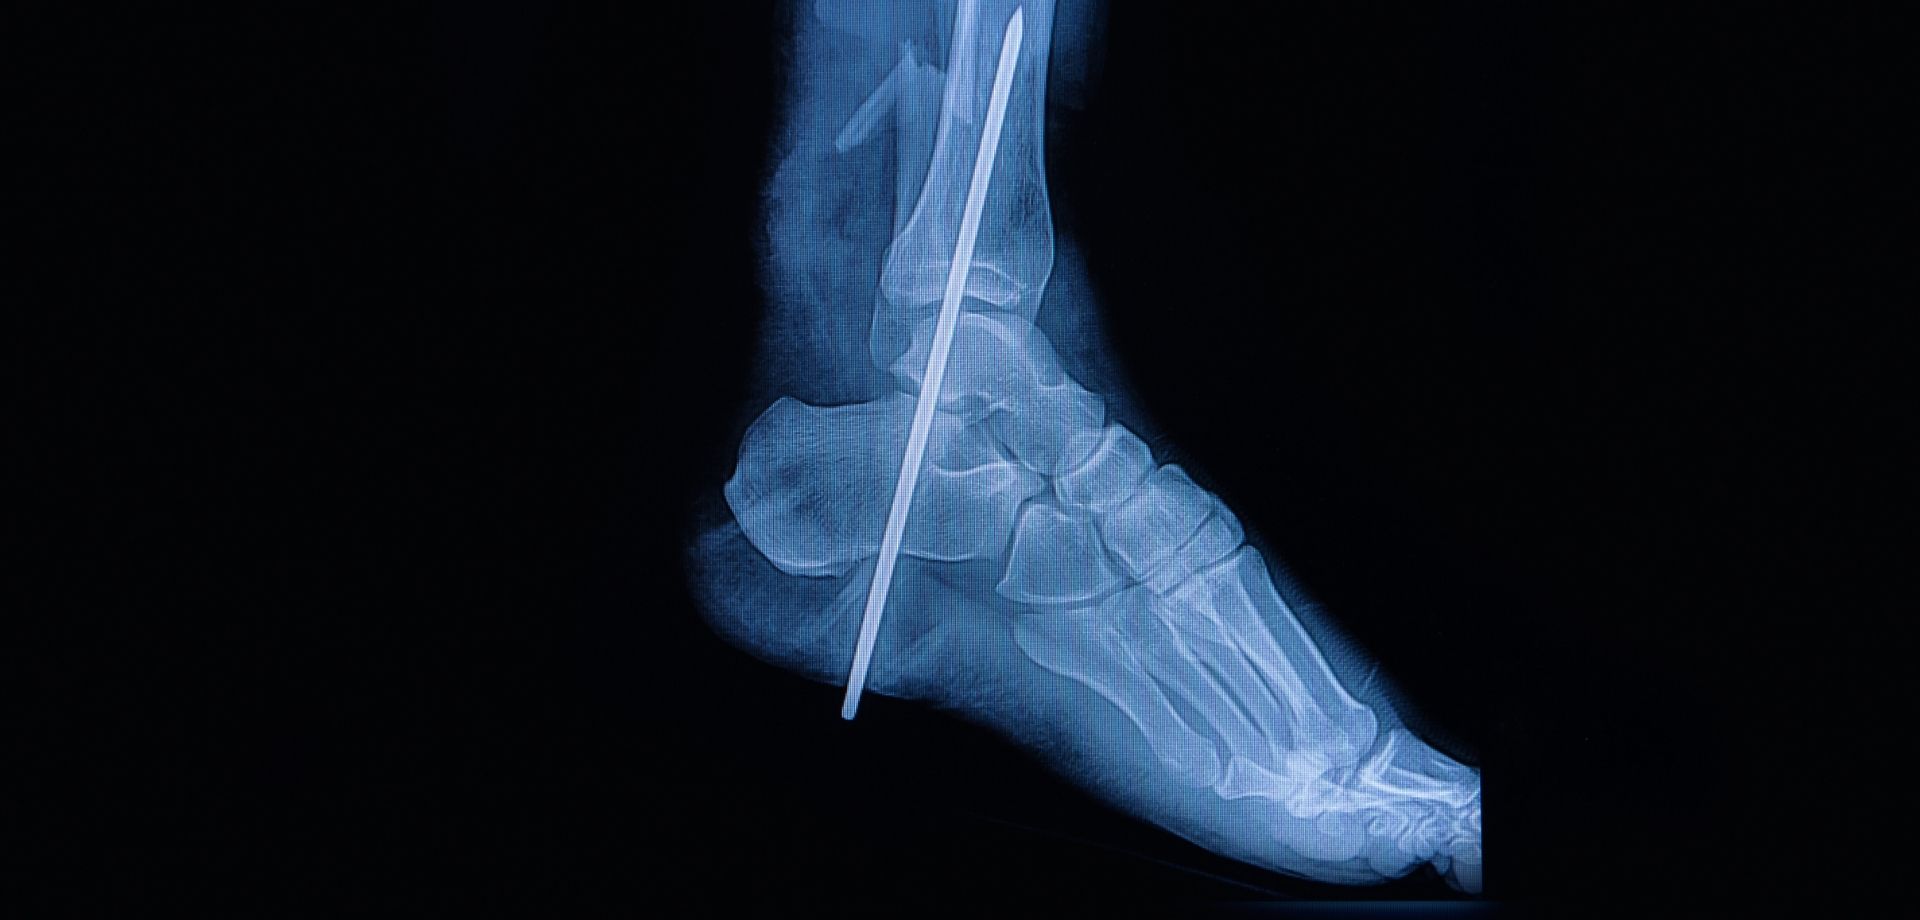

The department offers a full spectrum of non-surgical and surgical orthopedic services, with a strong emphasis on minimally invasive techniques. Advanced procedures such as arthroscopy, minimally invasive and endoscopic spine interventions, and modern fracture fixation methods are used to reduce surgical trauma, minimize pain, and promote faster recovery with shorter hospital stays. These approaches allow patients to return to daily activities and work more quickly, while maintaining high standards of safety and clinical outcomes.

Sports medicine is an integral component of the department’s services. We manage acute injuries, overuse conditions, and degenerative joint problems commonly seen in athletes and physically active individuals. Conditions involving the knee, shoulder, ankle, hip, and spine are treated through a coordinated approach that combines medical management, targeted rehabilitation, and, when necessary, surgical intervention. Rehabilitation programs are carefully structured to restore strength, flexibility, balance, and performance while reducing the risk of re-injury.